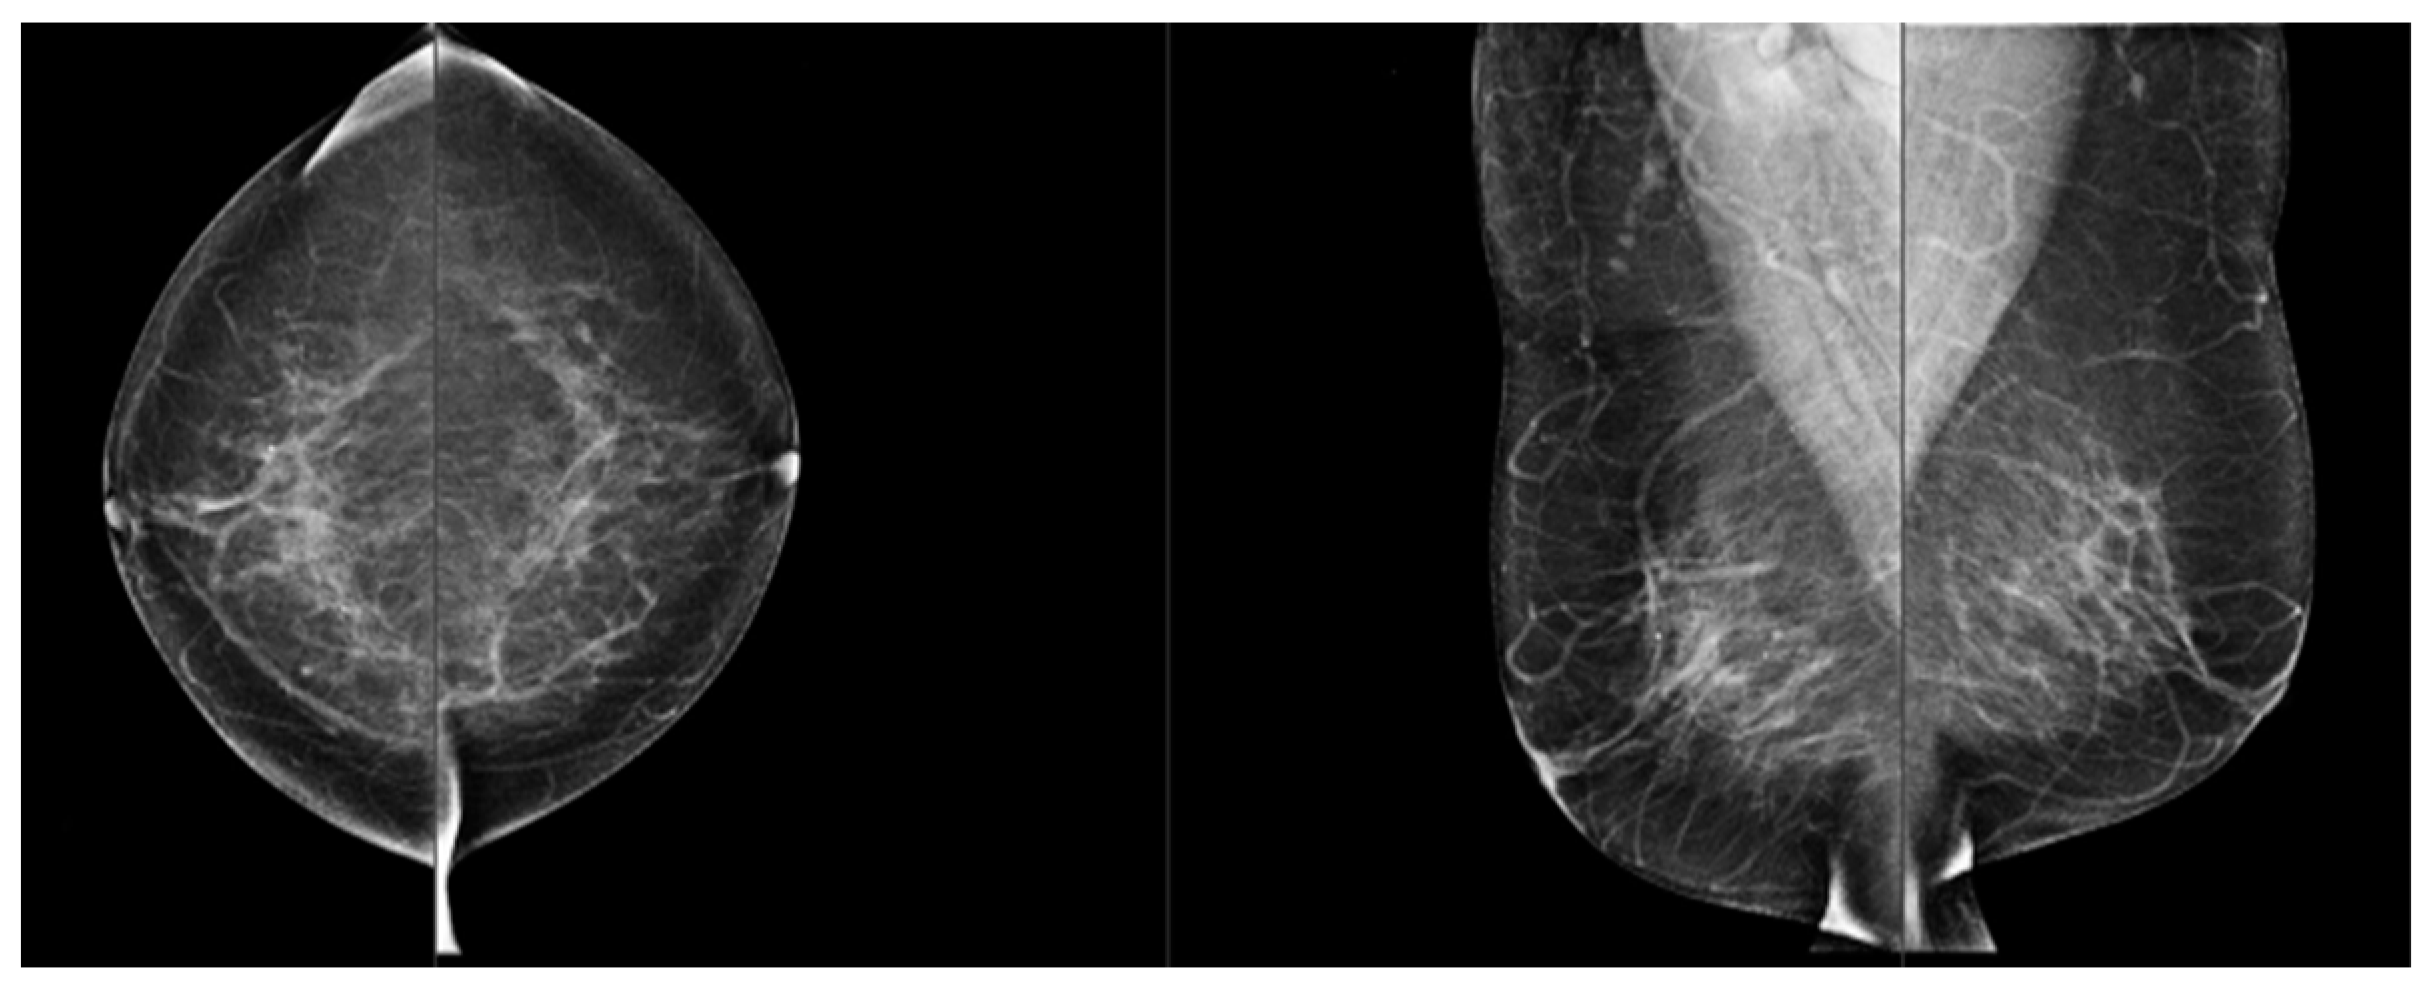

Comparison of Visual and Quantra Software Mammographic Density Assessment According to BI-RADS® in 2D and 3D Images

2. Materials and Methods

2.2. Image Acquisition

2.3. Software for Automatic Breast Density Assessment